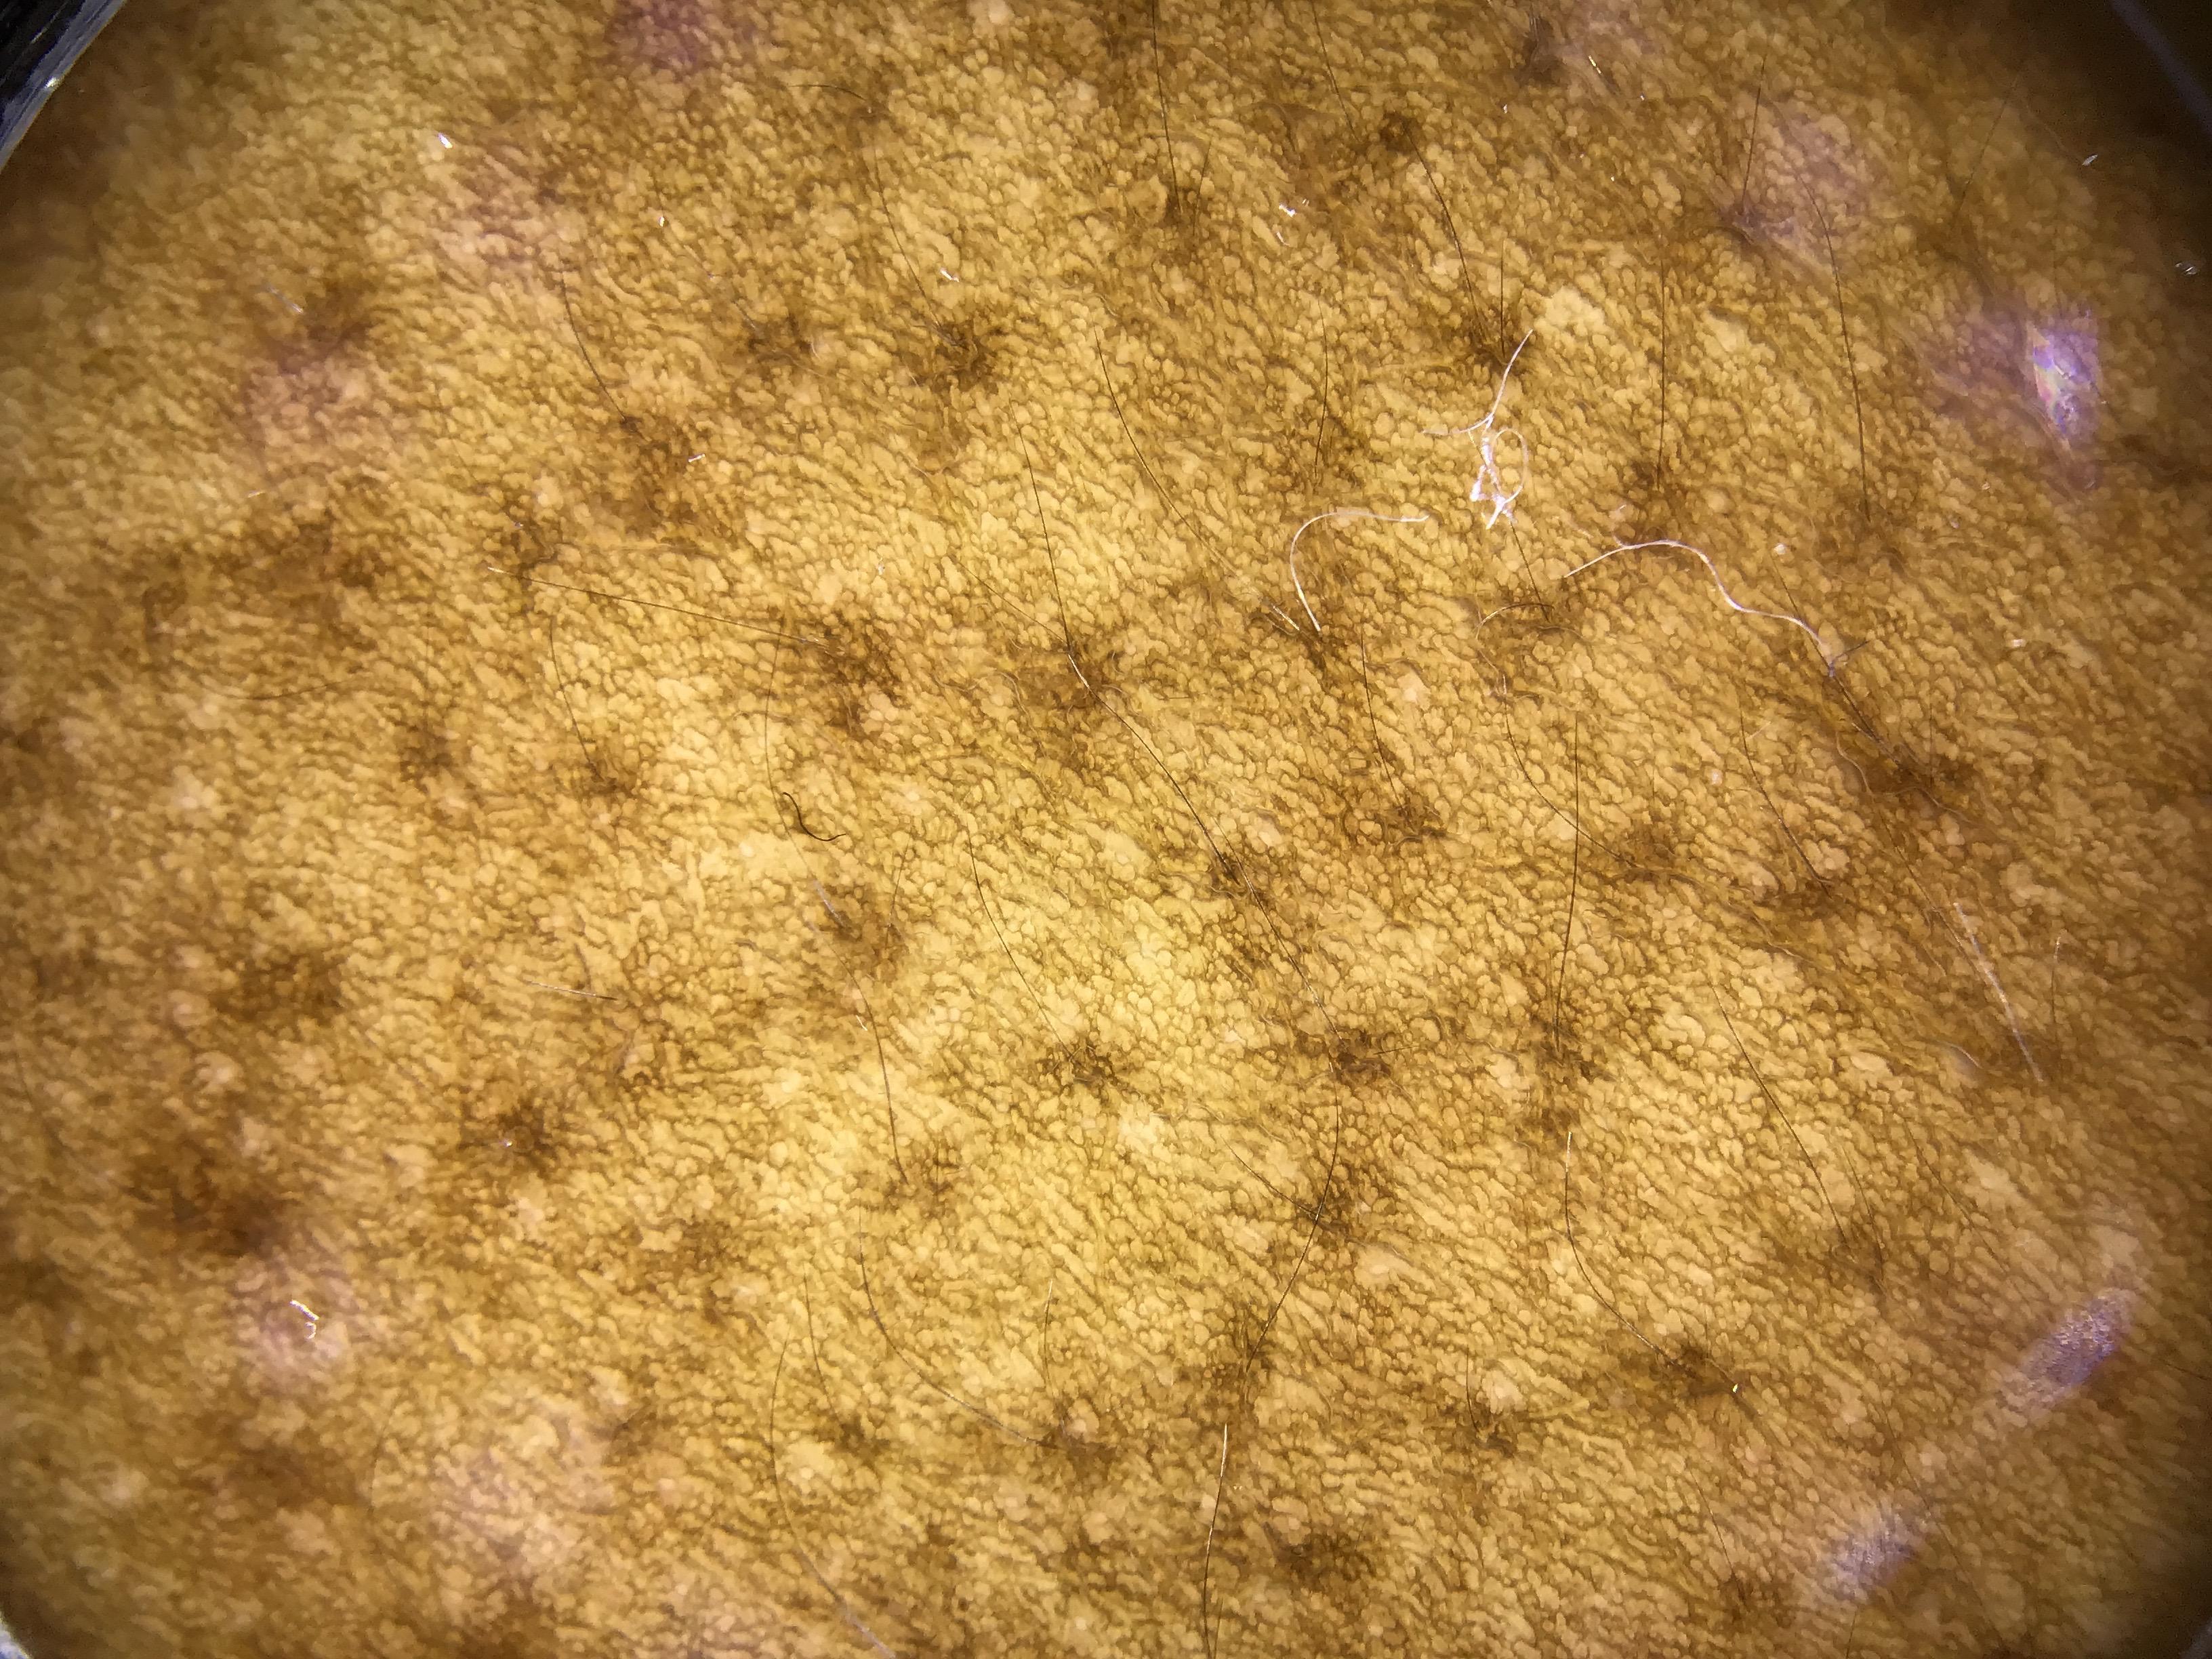

The dataset comprises both patient-level and site-level metadata for skin tone classification using the Fitzpatrick Skin Type scale, Monk Skin Tone scale, Pantone SkinTone Guide, and colorimeter readings (SkinColorCatch, Delfin Technologies). A total of 4,879 dermoscopic images are included. Skin tone assessments were collected across both lesional and non-lesional (normal skin) sites, mapped to standardized anatomic locations. All skin lesions are assumed to be benign, as they were imaged immediately following dermatologic evaluation.